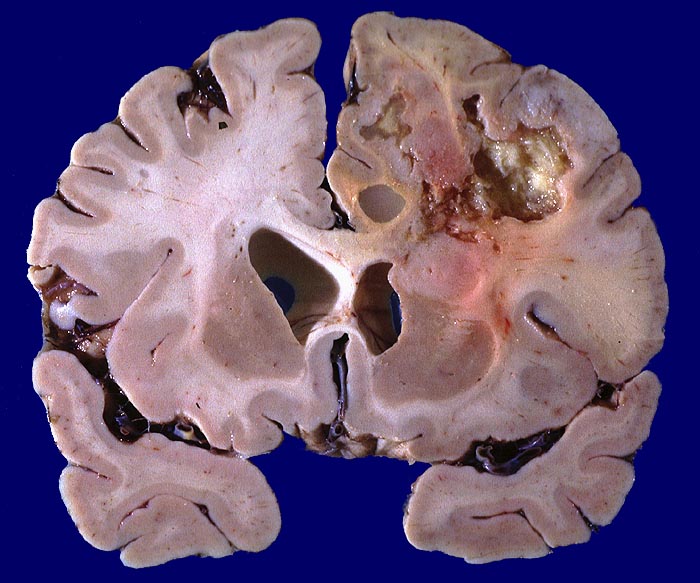

PathoPic ID 766 - Glioblastoma multiforme

Glioblastoma multiforme

maligner Tumor

Hirn parietal

Nervensystem

Bunte Tumorschnittfläche im parietalen Marklager mit ausgedehnten teils zystischen Nekrosen und unscharfer Begrenzung.

Frontoparietal zystische Nekrosehöhle Durchmesser 6cm. Infiltration von Nc. caudatus, Corpus callosum und Capsula interna rechts.

Hirntumor bekannt seit einem Jahr

Makroskopie

64